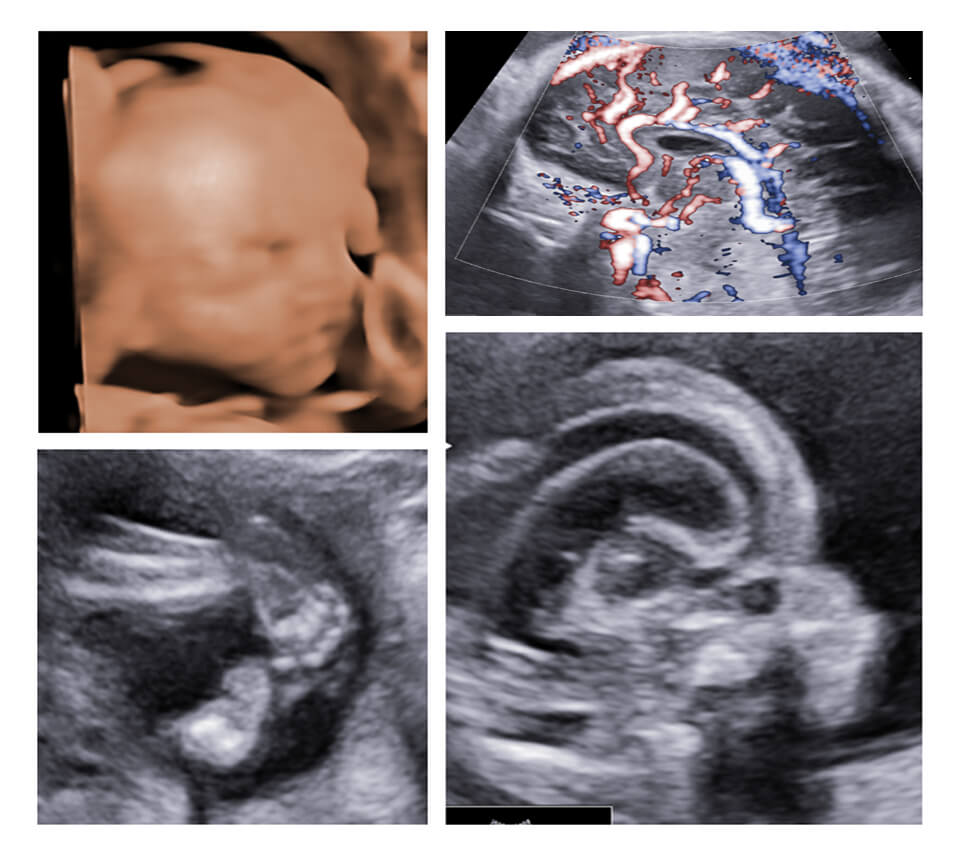

FIRST TRIMESTER (11-14 WEEKS) USG

WEEK 1 SCREENING : STRATEGY AND APPROACH

WEEK 2 NT SCAN: THE CORRECT APPROACH

WEEK 3 NB/ICT ASSIGNMENT SUBMISSION

WEEK 4 DV/TR/UTERINE ARTERIES ASSIGNMENT SUBMISSION

WEEK 5 STRUCTURAL SCAN REVISION & ASSIGNMENT SUBMISSION

WEEK 1

LEARN THE CONCEPTS OF BIOCHEMICAL SCREENING

UNDERSTAND STRATEGIES OF SCREENING

APPRECIATE AND LEARN LOW, INTERMEDIATE AND HIGH RISK

LEARN ABOUT THE BEST SCREENING MODALITIES

WEEK 2

LEARN THE CORRECT MAGNIFICATION

WHAT DOES A THICK NT MEAN

WHAT AFTER A THICK NT

WHAT ALL TO SCREEN FOR WITH A THICK NT

WEEK 3

LEARN THE CORRECT MAGNIFICATION FOR NT/ICT

WHAT AFTER AN ABSENT/HYPOPLASTIC NB

WHAT DOES AN ICT REFER TO

WHAT IS THE IMPORTANCE OF ICT

WEEK 4

LEARN THE CORRECT TECHNIQUE FOR DV/TR

WHAT DOES ABSENT A WAVE MEAN

WHEN DO YOU CALL IT TR

WHAT AFTER AN ABNORMAL DV/TR

PREECLAMPSIA SCREENING

MEAN UTPI CALCULATIONS

WEEK 5

ALWAYS DETECTABLE 9 ANOMALIES

PHYSIOLOGICAL/PATHOLOGICAL

ANOMALIES YOU CAN MISS

SIGNS OF ANOMALIES

PROGNOSTICATION OF ANOMALIES